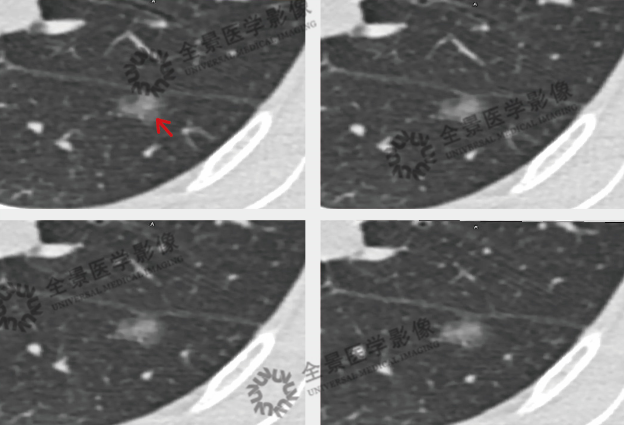

案例:中年女性,体检行肺部扫描时偶然发现,左肺下叶背段磨玻璃密度结节,诊断不明确。

行靶重建后显示:长径约0.9cm,呈浅分叶状,CT值平均约-410HU,邻近胸膜略凹陷。

结论:本中心根据上述形态学特征诊断为微浸润性腺癌,与手术病理结果相符。

横断面靶重建

矢状面靶重建